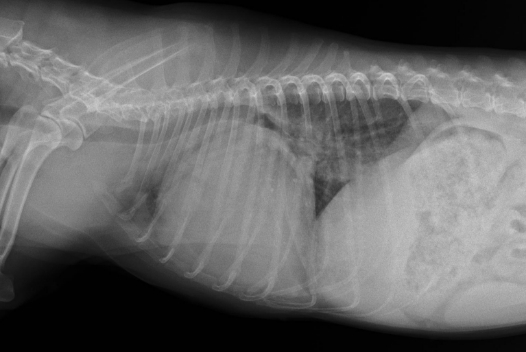

胸部X線検査(心臓の大きさや肺の状態の評価)

■心臓レントゲン 異常